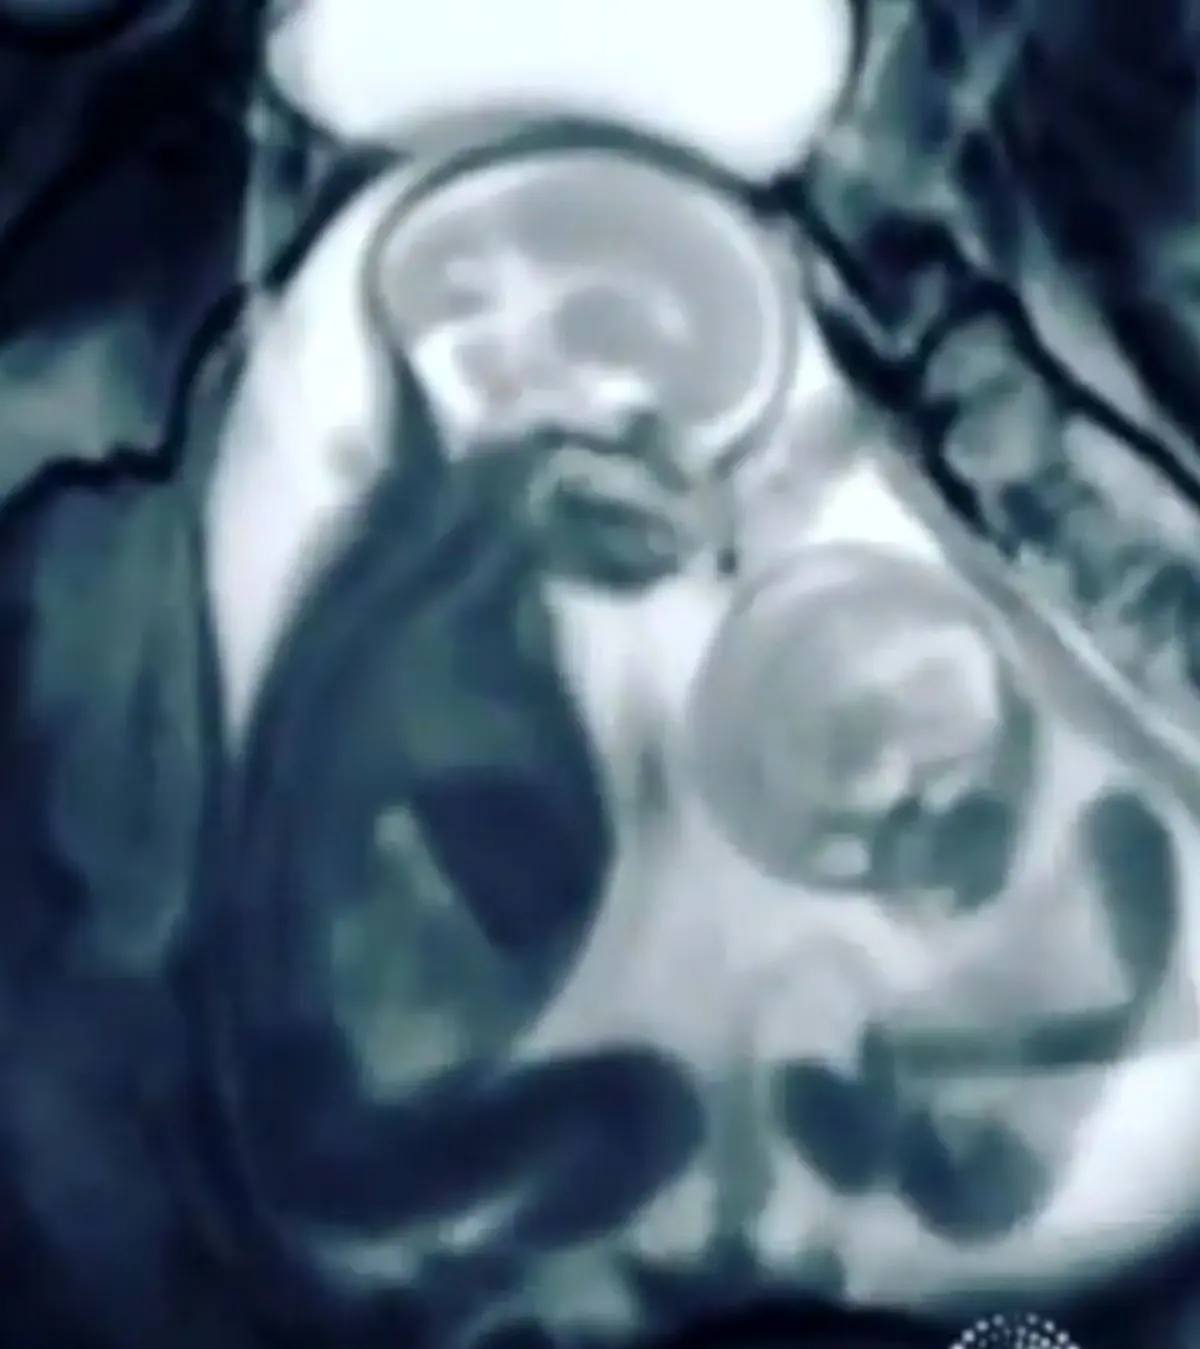

فیلم| کتک‌کاری عجیب دوقلوها در رحم مادر

مادری که برای بررسی وضعیت سلامتی جنین‌های خود به یک مرکز سونوگرافی مراجعه کرده‌ بود، متوجه درگیری بین دو جنین خود شد.